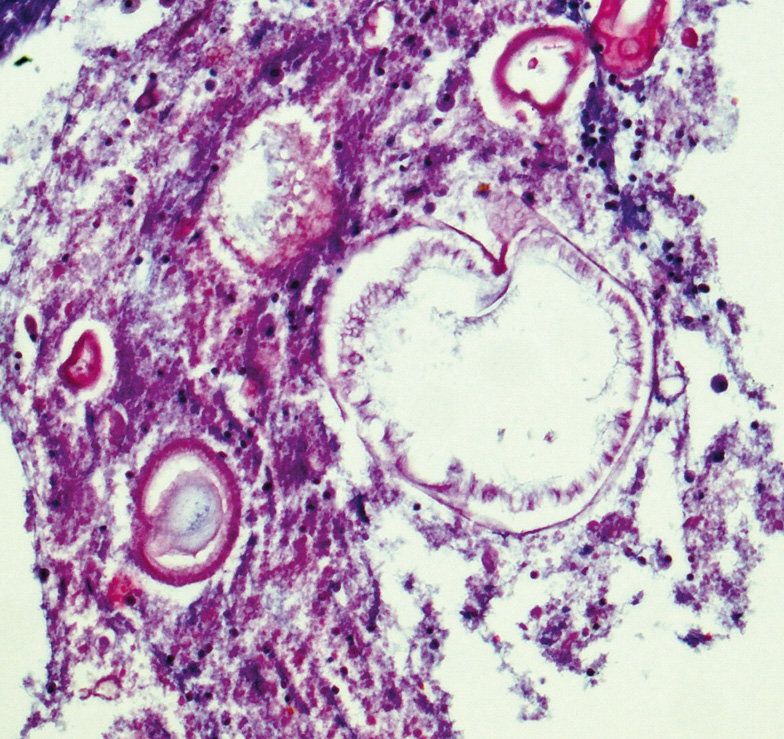

Повторное гистологическое исследование образований мягких тканей нижних конечностей показало гнойно-грануляционное воспаление, в воспалительном детрите были найдены множественные округло-овальные гидатиды с отчетливой хитиновой оболочкой и перифокальной кальцификацией, в просвете части гидатид определялись сохраненные сколексы (рис. 3). Согласно заключению патоморфолога гистологическая картина наиболее вероятно соответствовала эхинококковому гнойно-деструктивному поражению суставов и мягких тканей нижних конечностей, что определило перевод пациента в инфекционную больницу, где при дообследовании тесты на серологические маркеры эхинококкоза (определение антител к эхинококку методом иммуноферментного анализа) показали отрицательные результаты. Несмотря на данные серонегативного теста на антитела к эхинококку назначено лечение, направленное на элиминацию эхинококка (пациент получал Альбендазол по 600 мг/сут 18 дней). После дообследования в инфекционном отделении пациент был переведен в многопрофильный стационар с септическим отделением, где несмотря на лечение антибактериальными препаратами широкого спектра действия у него появилась и быстро нарастала полиорганная недостаточность, развивались признаки сепсиса, и в ноябре 2017 г. наступил летальный исход.

Рис. 3. Гистологическое исследование кожно-мышечного лоскута правого бедра пациента, окраска гематоксилин-эозин. Определяются гидатиды с отчетливой хитиновой оболочкой и перифокальной кальцификацией, в просвете части гидатид определяются сохраненные сколексы